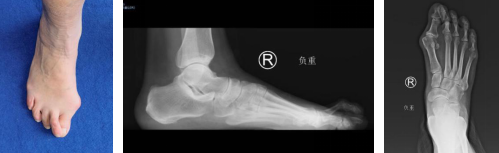

27岁的小徐,7年前出现左足踇外翻畸形,一年前行走时感觉疼痛,反复发作,发展到轻微跛行,这对于爱美的小徐难以接受,前来就诊。

门诊医生给小徐检查,左侧前足变宽,第1跖骨头内侧突出,诊断为左足踇外翻畸形(中度),石院长团队经过讨论,决定采用微创踇外翻技术为其矫形。

51岁的张大姐,右足踇外翻畸形10年,第一跖趾关节间断性疼痛,越来越严重,听从朋友家人建议后,来到betway在线登陆足踝科就诊。

门诊医生检查,张大姐右足踇外翻畸形,踇囊炎,右足第2趾爪形趾,想要消除疼痛,需要进行矫形治疗。

术前